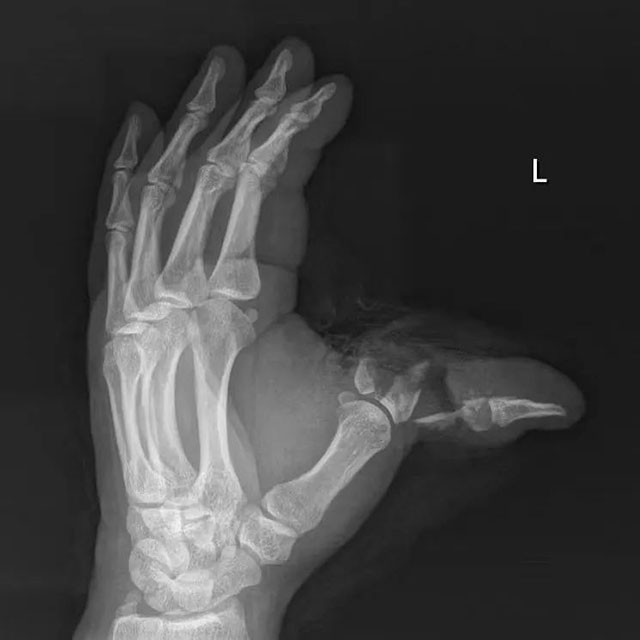

【移花接木】泸州男子手指被砸断,医生从腰上取骨和肉……

清晨,41岁的赵大哥像往常一样在工地作业,殊不知意外即将来临。就在赵大哥搬运几块大石头时,石头从上边滑落,狠狠砸中他左手拇指,工友紧急将他送往当地医院救治。医生接诊后,见赵大哥伤势较重,为其进行了简单包扎后,建议转入上级医院继续治疗。于是赵...